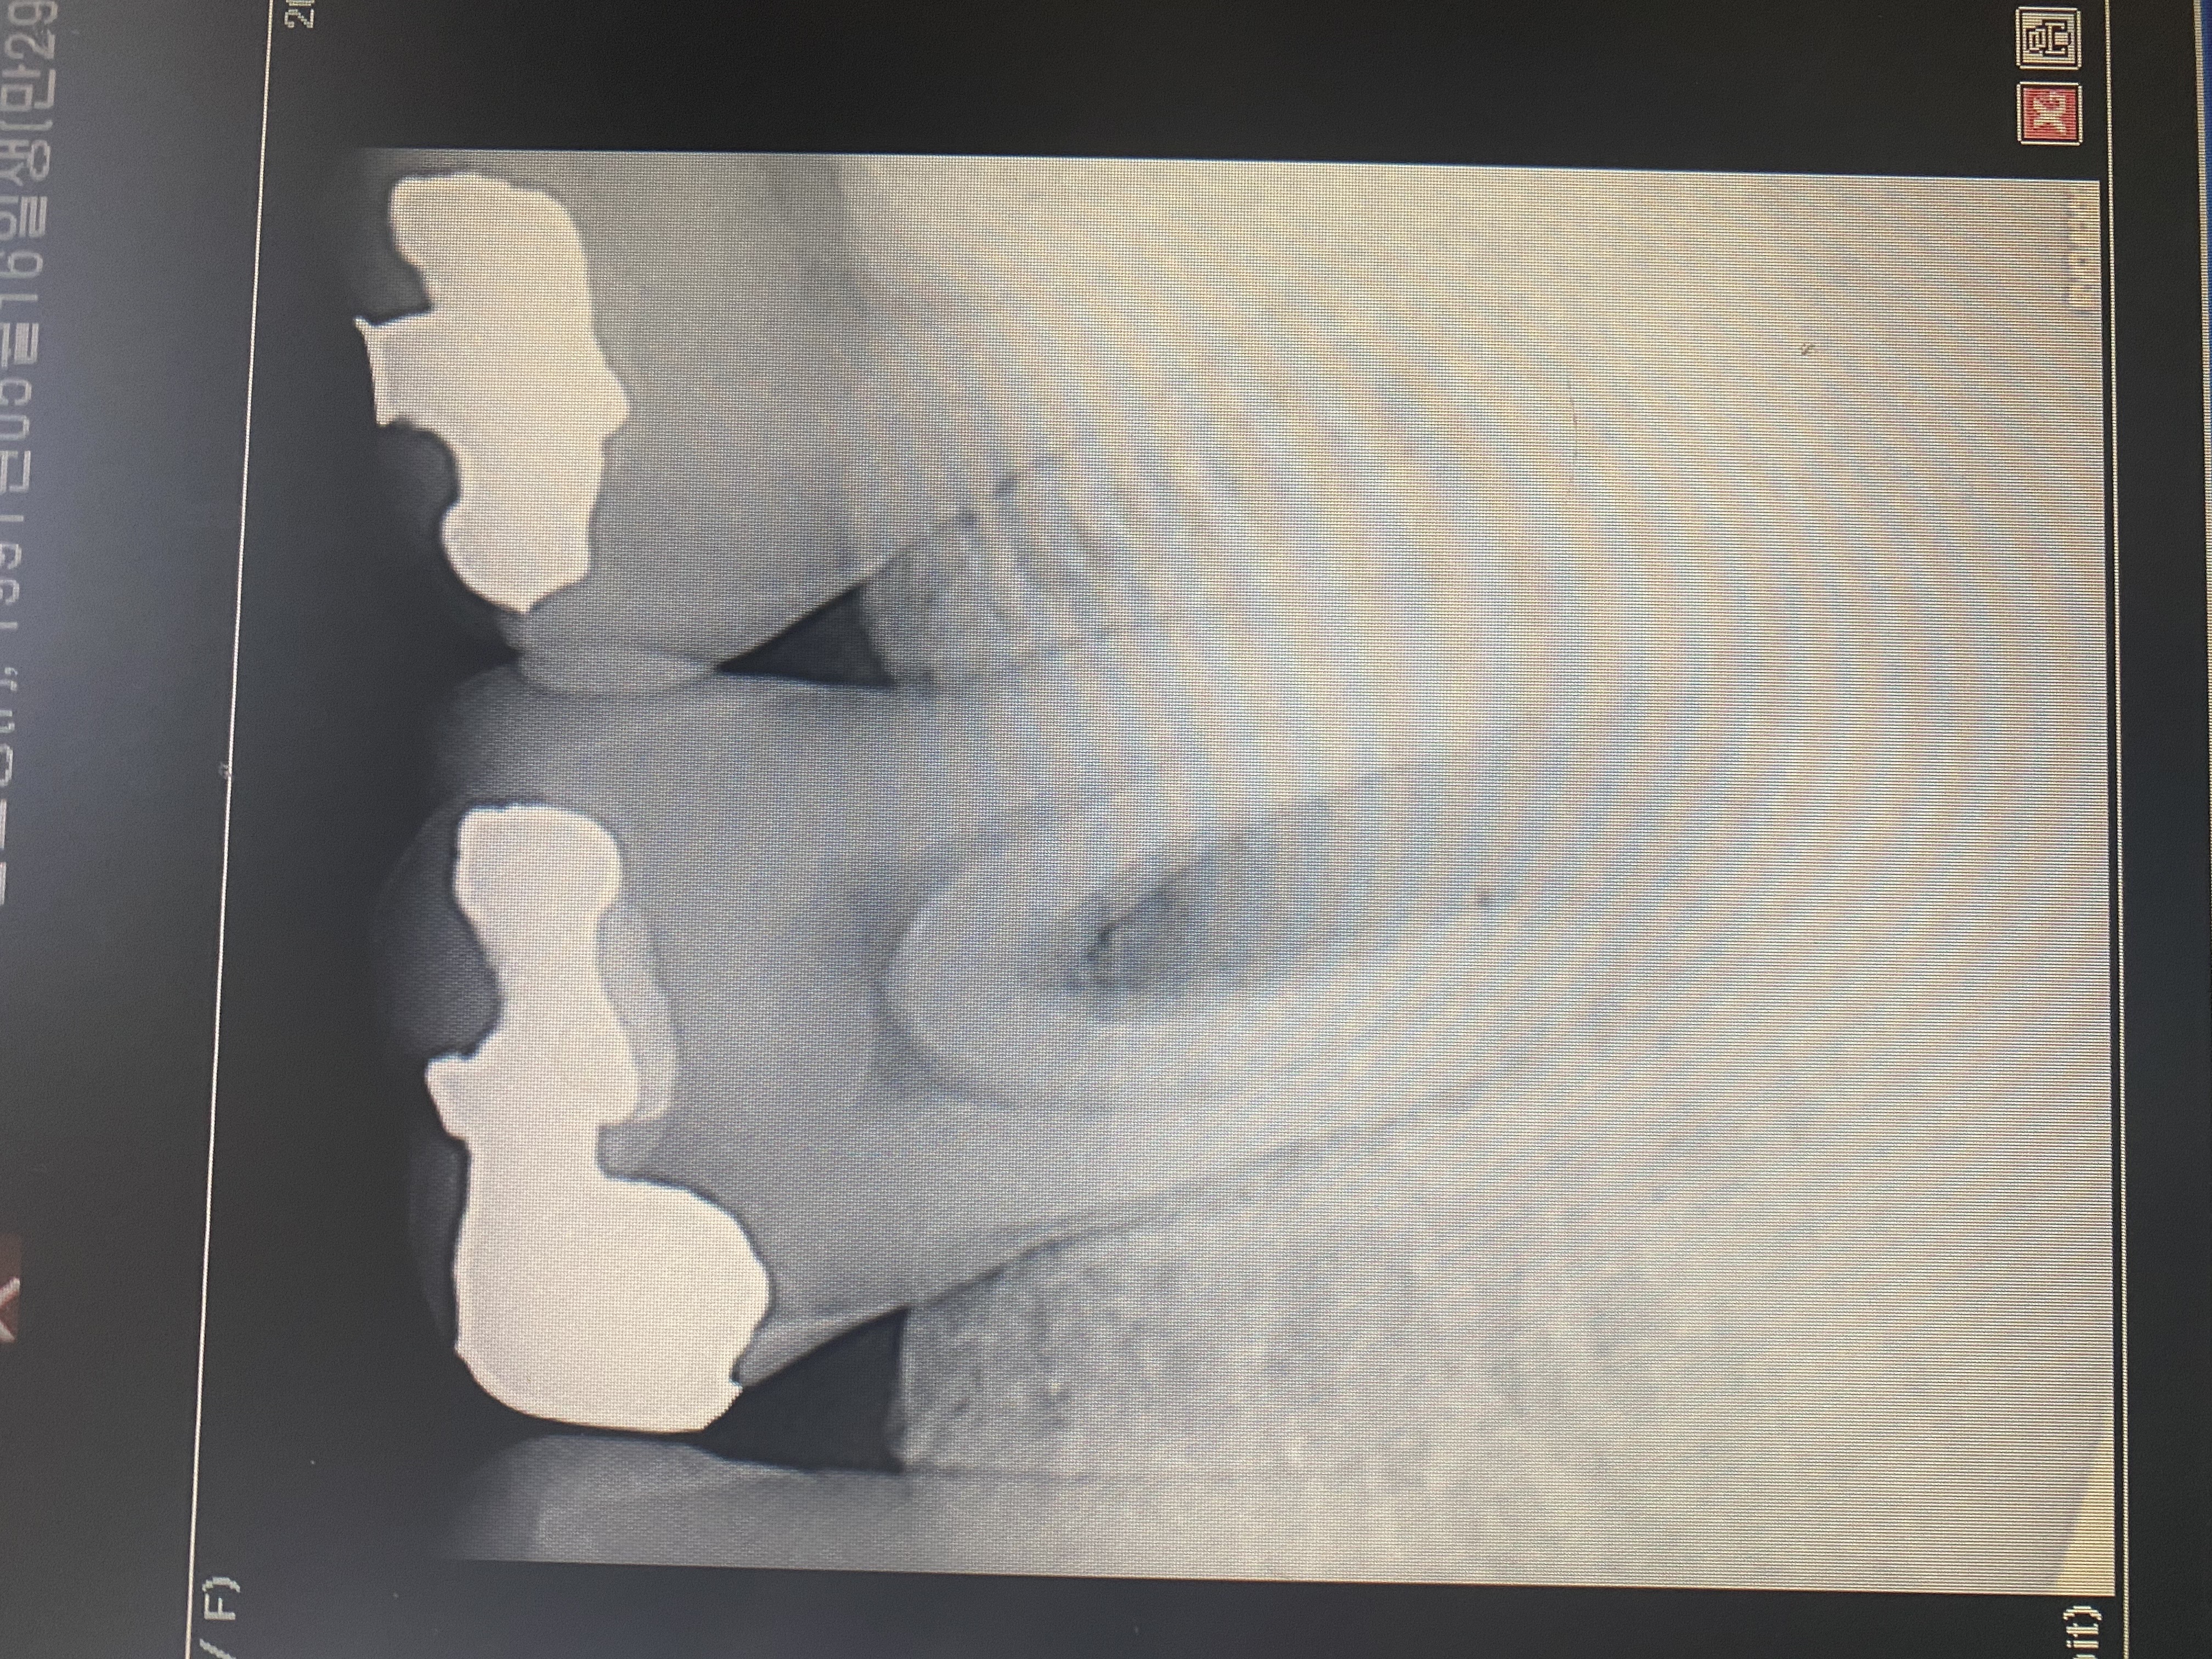

안녕하세요 선생님. 몇해전 선생님 조언으로 많은 도움을 받았었습니다. 이번에 가족이 통증이 있어 치과에 방문했는데 신경치료 또는 임플란트를 추천하더라고요. 제가보기에는 문제의 치아보면 치아부분에는 검게변하지 않아서 충치가 안보이는거 같은데 병원에서는 신경치료나 임플란트를 권하네요. 뿌리끝에도 검은 부분이 없는거 같고요. 뿌리사이에는 검게 염증이 보이는거 같습니다. 사진상으로 정확한 진단은 힘드시겠지만 조언좀 부탁드립니다. 2년전 선생님 말씀대로 신경치로안받고 저도 별다른 통증없이 잘 관리하면서 치아를 사용하고 있어서 항상 감사드립니다.

• 작성자hyuntae 작성자 본인 여부 작성자 | 작성시간 21.05.01 선생님 조언 감사드립니다. 염증이 심한건가요? 보통 검게 나오는게 염증으로 알고 있는데 사진상으로는 뿌리끝은 하얀거 같고 뿌리 사이가 검은거 같은데 그쪽이 염증이 심한건가요?